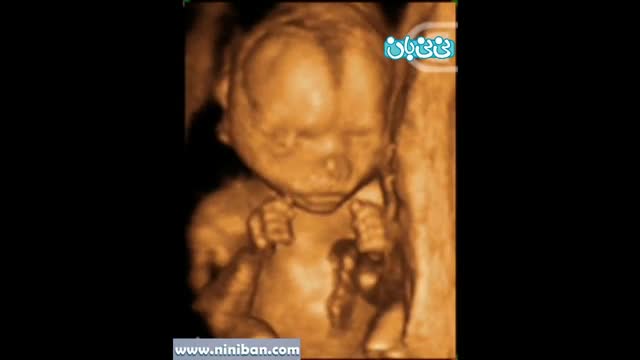

سونوگرافی چهار بعدی در بارداری هفته هجدهم